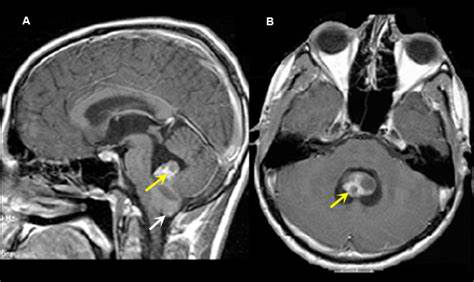

建议术后立即进行脑部核磁共振扫描,较好在手术后24-48小时内进行,以确定手术范围。如果在术后核磁共振成像上出现广泛的肿瘤负担,并且残留的疾病可以容易地切除,几个小组已经提出了二次手术以较大化手术切除的范围。除了提供组织诊断和好转预后外,肿瘤切除还可缓解脑积水,脑积水常见于一些幕上室管膜瘤,更常见于后颅窝室管膜瘤。在大多数患者中,切除原发肿瘤足以控制梗阻性脑积水,而无需进行脑室外引流或脑室腹腔分流术。

强烈室管膜瘤的分期,包括整个神经轴的成像和脑脊液分析。脑脊液分析应在手术后至少延迟2周,以避免脑脊液中出现混淆的结果。通过脑脊液传播并不常见,估计有15%的患者会发生这种情况,但这将影响治疗计划。